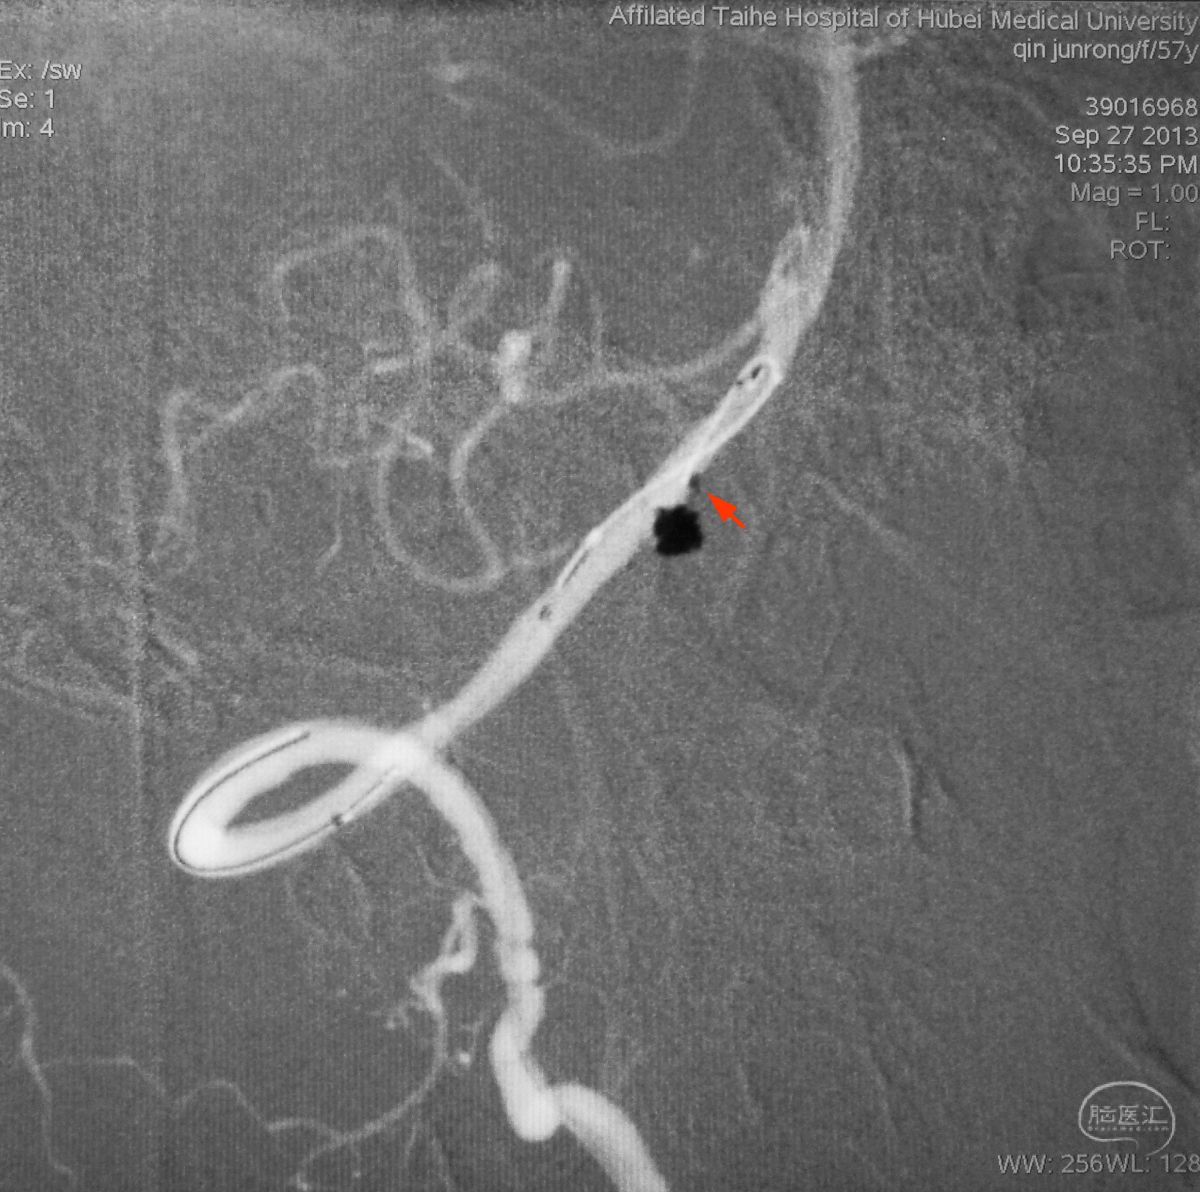

依次送入QC-2-4-3D,2-3-Helix,1.5-2-Helix,1.5-2-Helix四枚弹簧圈,最后一枚弹簧圈将管头(箭头)顶出瘤腔。

将Traxcess 14微导丝送入微导管,稍向远心端送微导管,使管头远离动脉瘤,再缓慢撤离。